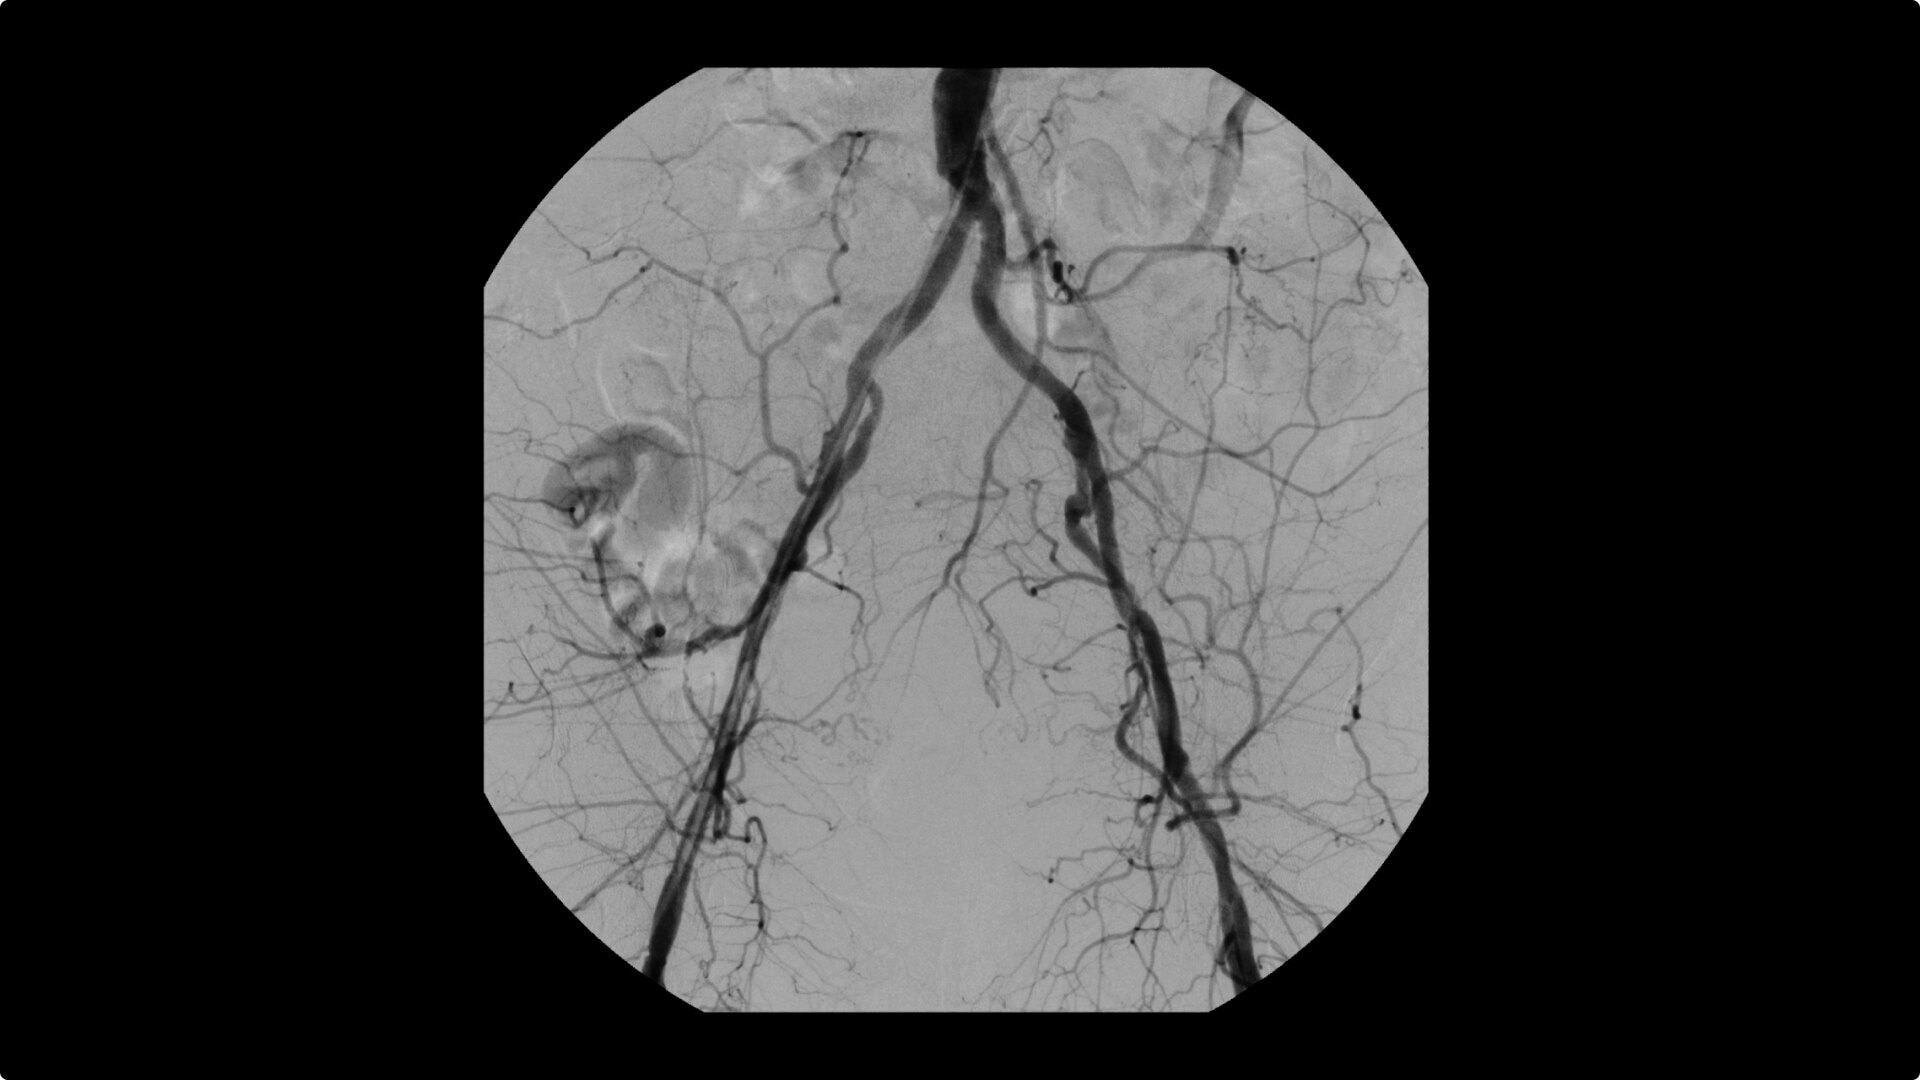

Perform a full leg Bolus Chase in one contrast run with a Preset Profile that includes Motion Tolerant Subtraction, that dynamically adjusts image quality based on presence of motion.

During contrast run-off procedures, easily select contrast type with positive (e.g. Iodine) or negative (e.g. Carbon Dioxide) during subtraction. The OEC Elite CFD cardiovascular package also includes Roadmapping.